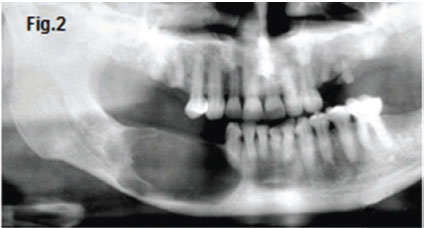

This thirty five year old male patient presented with a slow growing swelling in the right body of the mandible (Fig.1).The patient also experienced intermittent pain from time to time in the region of the swelling. What are the most important radiological features and what is your diagnosis?

The cropped pantomograph and postero-anterior image (Figs.2 & 3) of the patient show a homogenous radiolucency in the right mandibular premolar and molar regions. Note the extensive calcification present in another case and the apparent dentigerous relationship to an impacted and displaced mandibular canine (Fig. 4). A histological diagnosis of a calcifying odontogenic cyst (COC) was made. The calcifying odontogenic cysts are developmental odontogenic lesions which are believed to arise from odontogenic epithelial remnants in the gingivae or in the mandible or maxilla. Over the years since its first description, it has become clear that the COC has a number of variants, including features of a benign odontogenic tumour. The COC was first described by Gorlin et al. (1962, 1964) who were impressed by the significant presence of so-called 'ghost cells' and its histological resemblance to the cutaneous calcifying epithelioma of Malherbe. The eponym of 'Gorlin cyst' is frequently used. Since its early description the lesion has been widely recognised, occurring both peripherally and centrally in the jaws, while its origins, pathogenesis and histopathological variations have evoked considerable discussion in the literature. Patients range widely in age (1 to 87 years) with a peak incidence for detection in the second decade of life. Some reports suggest that the cysts have a predilection for females, whereas other studies show no gender bias. More than 70% of COC are associated with the maxilla. The anterior segments of the jaw are most commonly affected. The calcifying odontogenic cyst may appear initially as a unilocular or multilolcular radiolucency with discrete, well demarcated margins. Irregular sized calcifications may be scattered in the radiolucency, producing variable degrees of opacity. This may produce a "salt and pepper" appearance. Denser opacities are likely to be present if the cyst is associated with a complex odontoma. The COC is treated by surgical enucleation unless it is associated with another odontogenic tumour in which case wider excision may be required.